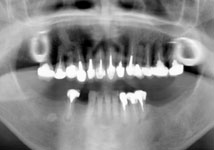

虫歯と歯周病が進行し、歯が動揺して噛みにくいということで受診されました。

歯周再生治療と審美補綴治療によってトータルコーディネートしました。

今では虫歯も治り、しっかり噛めるようになったと満足されています。 |